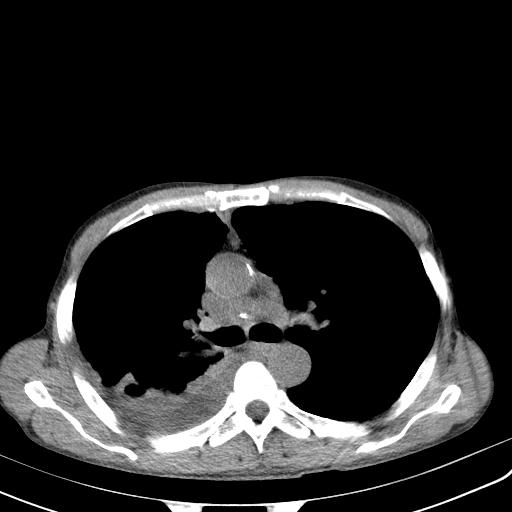

男性 75  咳嗽 一周前发热最高达39

右肺继发型tb并右侧tb性胸腔炎,右侧胸腔大量积液并右下肺膨胀不全,慢支肺气肿、多发肺大泡。建议抽胸水实验室检查并复查排除恶性在占位。

右上肺继发型肺结核,右胸腔中等量积液。

结核的基础上有纵隔淋巴结肿大,右侧有胸水,但右侧纵隔反而窄,说明有肺有不张。

再就是右下肺有块影,和不张混合,还是不能除外肺癌。

补充材料,患者2月份ct片大致正常,双侧胸腔积液,2月份抽胸水未发现ca细胞,现患者发热,痰多,各气管通畅,

1)右肺继发型肺结核。2)左肺胸膜下多发性肺大泡。3)右侧胸腔积液。